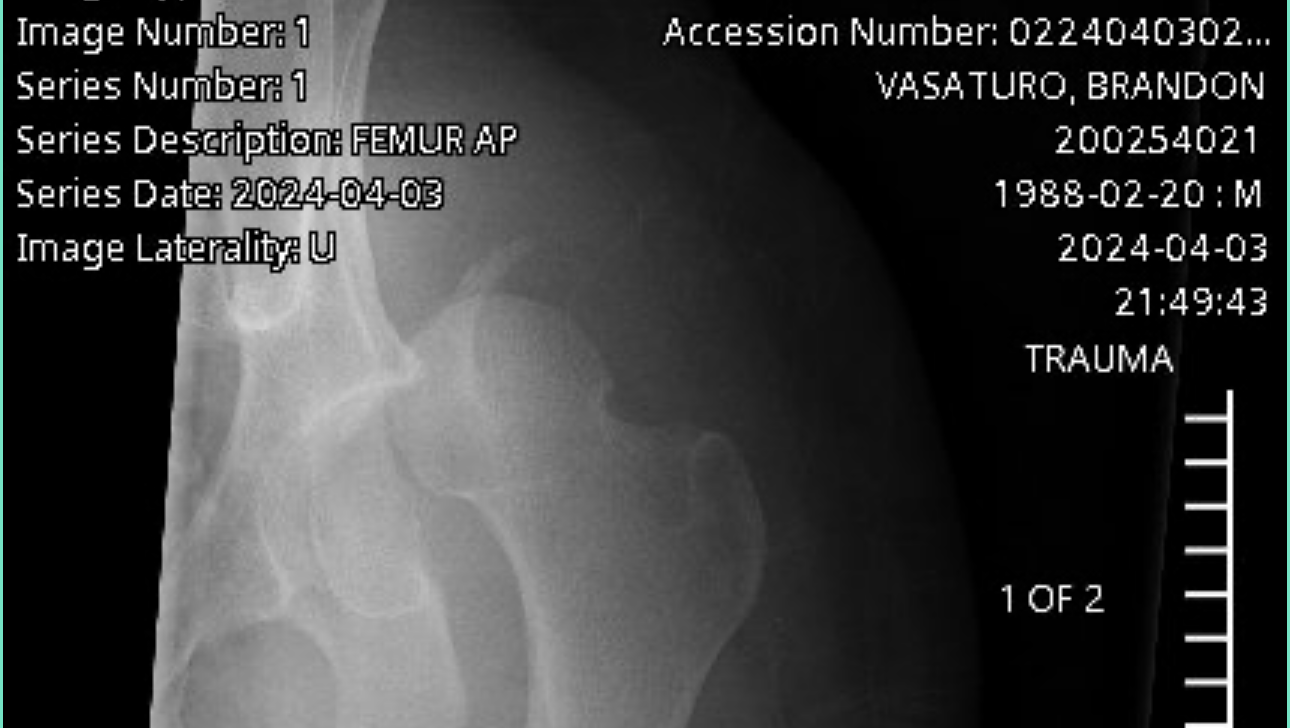

Once at the hospital, it was determined that he broke both of his arms and legs in multiple places, shattered his knee cap, broke his ribs, broke and dislocated his hip, and broke his femur. The only thing not broken is his spirit, pretty face, and desire to face this battle head on. Despite only being able to wiggle his fingers and toes, he still keeps us and the wonderful hospital staff laughing and is a true inspiration.

Brandon has been hospitalized since the accident and following multiple surgeries and some gnarly titanium all throughout his body, he is preparing to go to a rehabilitation center/nursing home to continue healing with months of physical therapy as he is not anywhere near being self-sufficient.